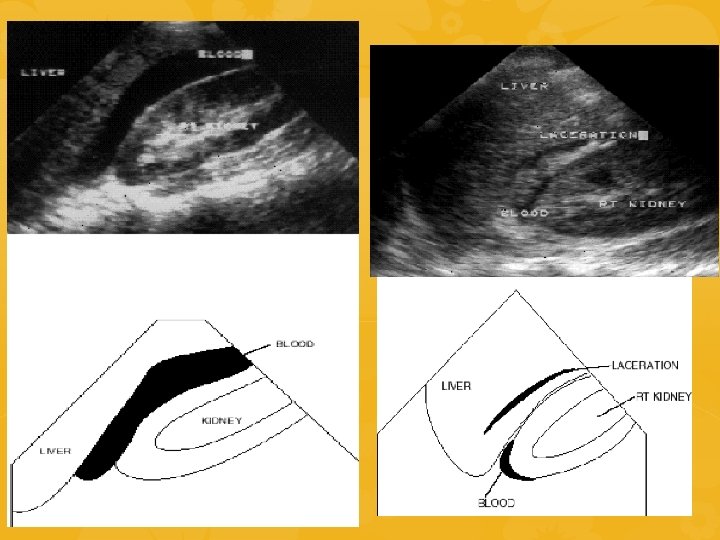

ECOFAST SCOPO: identificare raccolte ematiche nelle cavità del corpo dove non dovrebbe esserci Esplorazione 4 aree 1. QSD 2. Sottoxifoidea 3. QSS 4. Soprapubica INDICAZIONI NEL TRAUMA: • Emorragie toracoaddominali • Trauma penetrante toracoaddominale • Sospetto tamponamento pericardico • Paziente con ipotensione di ndd • Trauma toracoaddominale nella

• • QSD-Quadrante superiore destro Sonda poggiata sulla linea medioclavicolare sulla porzione inferiore della gabbia toracica o al di sotto del margine costale destro Ricercare del liquido anomalo ipoecogeno negli spazi potenziali